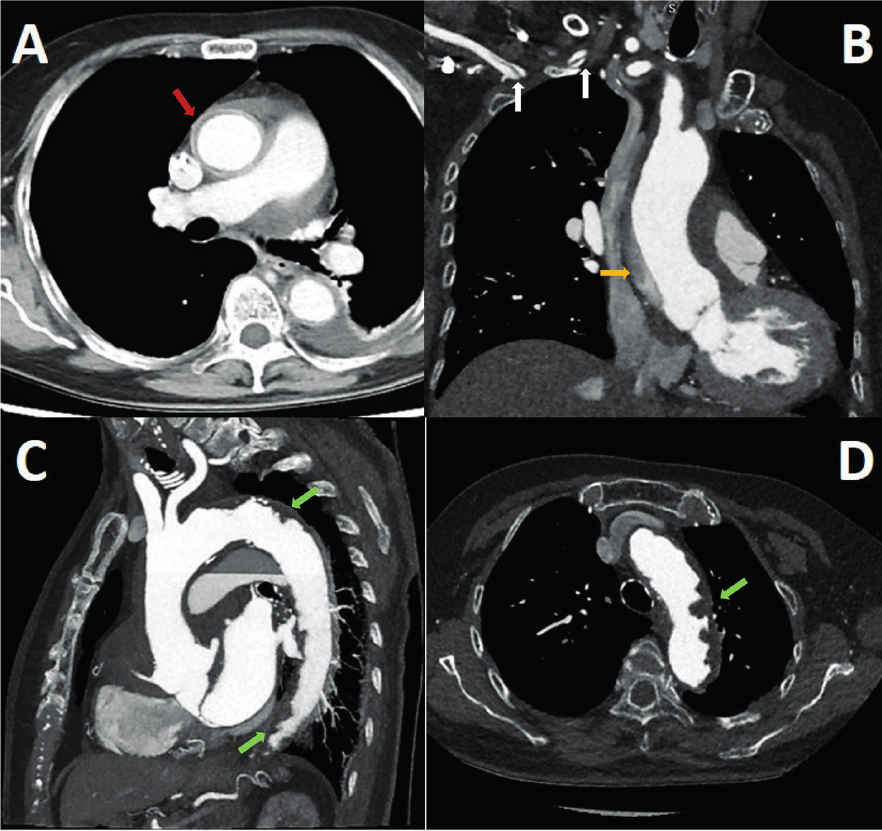

Figure 1

CT angiogram. A, B. Dissection flap is seen at the sinotubular junction (red arrow), with ascending trajectory to the proximal aortic arch (orange arrow) and extending through the brachiocephalic trunk to the proximal segment of the right subclavian artery (white arrows). C, D. Complicated plaques in the aortic arch and descending aorta (green arrows). Diffuse atheromatosis is observed at the aortic arch with an image suggestive of intraluminal thrombus.